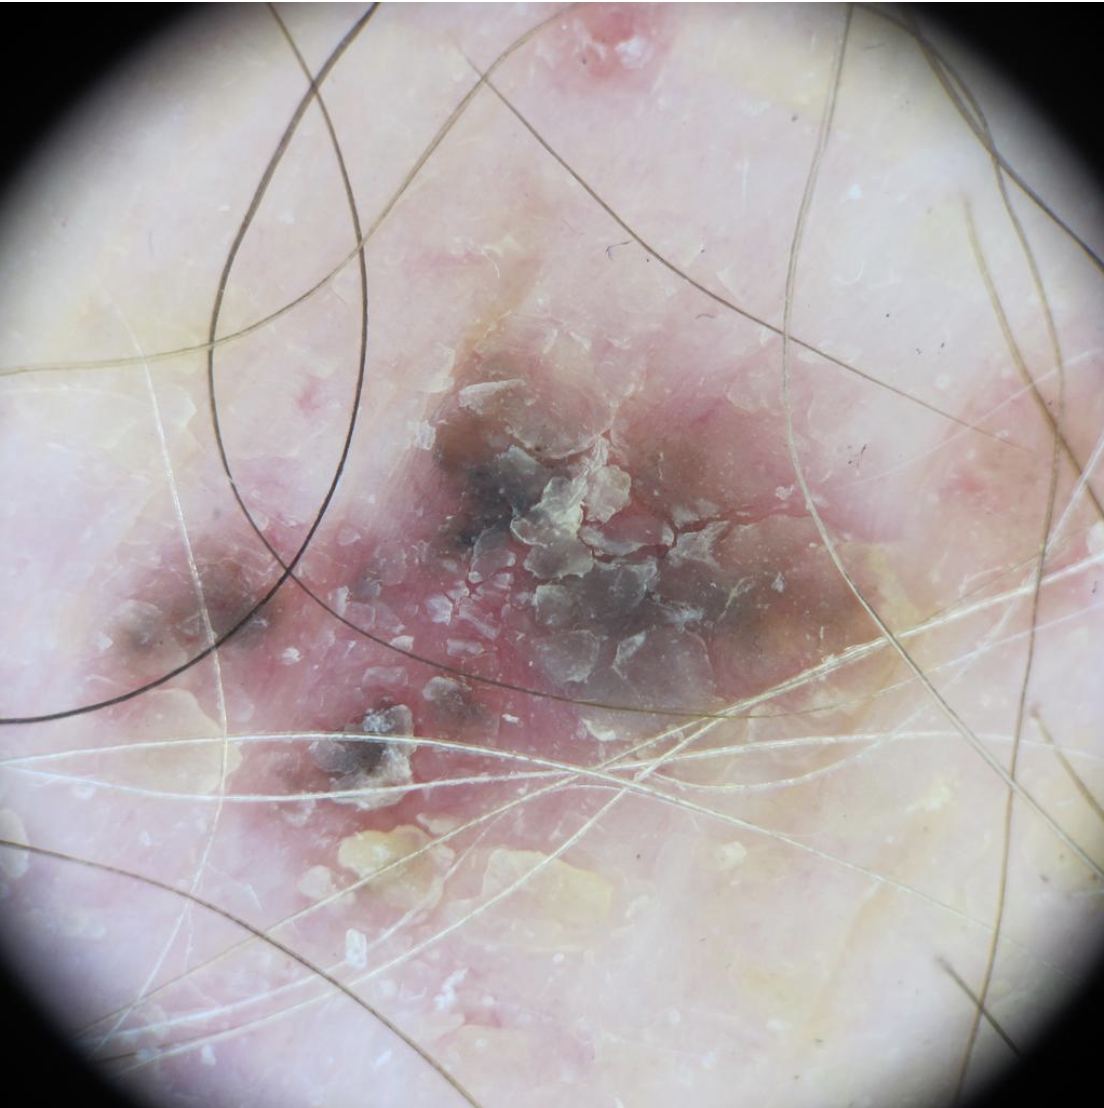

Basal cell carcinoma on the posterior torso. Photo: International Skin Imaging Collaboration at isic-archive.com